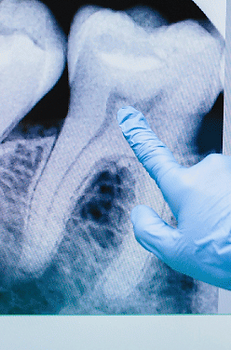

Root canal therapy is a remarkably minimally invasive procedure designed to save teeth that might otherwise require extraction. Contrary to outdated perceptions, modern root canal treatments typically cause minimal pain thanks to effective local anesthesia and advanced techniques.​

Experience tooth preservation with modern root canal therapy! Our advanced endodontic techniques deliver gentle, effective treatment that eliminates pain and saves teeth that would otherwise require extraction—all while keeping you comfortable throughout the procedure. Most patients are surprised by how quick and painless today's root canal treatments are compared to outdated perceptions.